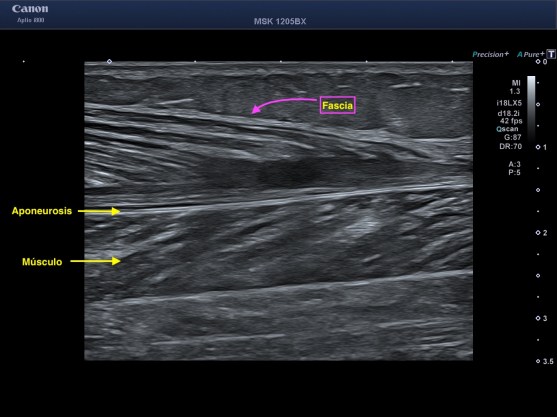

1. Músculo: El Rey, en torno a él se descibe todo ecográficamente. De modo muy general el músculo es compone de fibras musculares, estas fibras están rodeadas de tejido conectivo del endomisio y ellas se agrupan en fascículos rodeadas por perimisio que contiene capilares y terminaciones nerviosas.

El Permisio son esas bandas paralelas e hiperecogénicas y como el Epimisio, son hiperecogénicos.

Los Fascículos musculares son hipoecogénicos.

2. Aponeurosis: La aponeurosis es una membrana fibrosa formada principalmente por haces de colágeno que son hiperecogénicos y que tiene la función de servir de inserción a algunos músculos.

5. Fascia: Esta estructura de tejido conectivo que se extiende por todo el cuerpo es de apariencia membranosa, conecta y envuelve todas las estructuras corporales. Soporta, protege y da forma al organismo. Como la componen haces de colágenos (tejido conectivo) es de aspecto hiperecogénica.